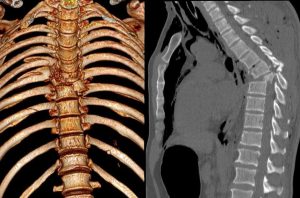

Диагностика включает сбор анамнеза и тщательный клинический осмотр. Инструментальные методы — рентгенограмма, КТ, особенно если речь идет об оскольчатых и осложненных переломах, для предоперационного планирования.